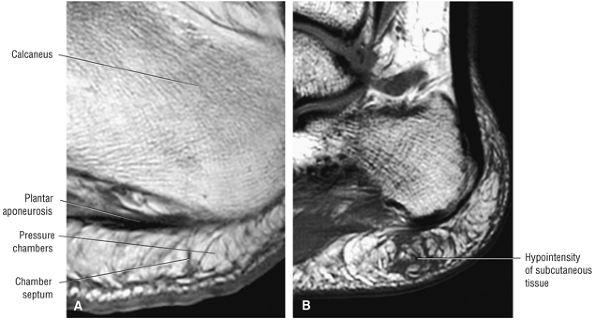

Inflamed synovium envelops the AITF and the inferior articulation of the tibia and fibula.

-

Synovitis may involve the anterior and posterior aspects of the syndesmotic ligament.

There may be associated loose bodies, chondromalacia, and osteophytes.

Bassett's ligament is a separate distal fascicle of the AITF and may be associated with syndesmotic impingement against the lateral talus.

and the lateral malleolus is pulled superiorly when the fibula is rotated medially (Fig. 5.219).